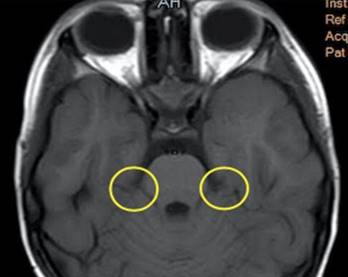

Se realizó una resonancia magnética cerebral con contraste en la secuencia T1, donde se identifica ausencia de nervios faciales en ángulos pontocerebelosos los cuales. Los conductos auditivos internos, nervios cocleares y nervios vestibulares de características normales, no se identificaron lesiones tumorales, ni alteraciones en senos venosos, hipófisis, hipotálamo, septum pellucidum o cuerpo. Los estudios de extensión como radiografía de columna vertebral, ecocardiografía transtorácica y cariotipo de bandeo extendido o de alta resolución, no evidenciaron alguna anormalidad (Figura 1).